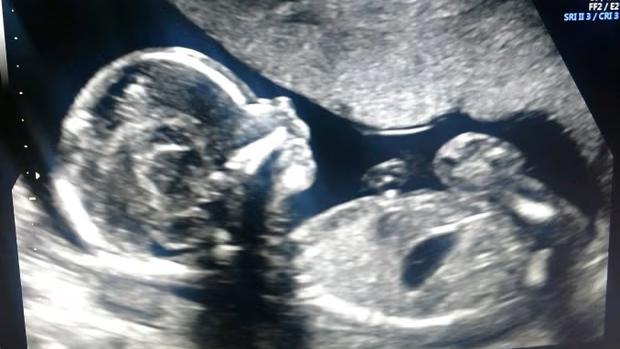

兩姐妹由2個精子分別與2個不同卵子同時受精的「異卵雙胞胎」,還要是「混血雙胞胎」2種機會極稀有情況同時發生,機率大約只有5億分之一,真是難過中六合彩。